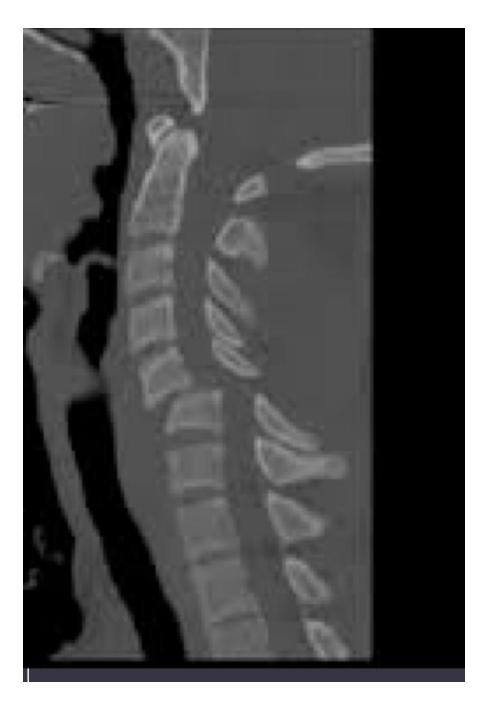

Which of the following is the mechanism of this injury; MOI?

- Flexion distraction injury

You are evaluating a 17 years old adolescent girl who was in an unrestrained motor vehicle accident. Imaging is demonstrated. And she has significant posterior midline neck pain. What is the diagnosis and MOI?

- Jumped facet Hyperflexion